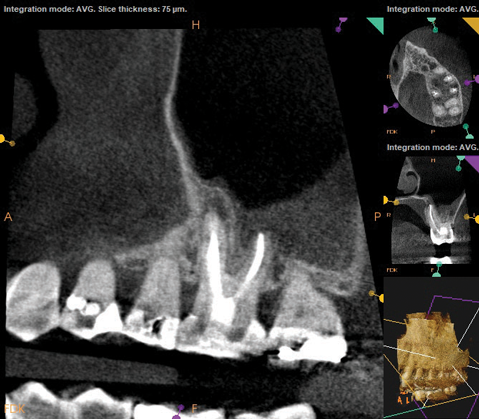

Periapical and CBCT imaging confirmed the presence of apical pathology, as well as a dramatic sinus communication with MSEO (Figure 1 and Figure 2). The diagnosis for tooth No. 13 was pulpal necrosis with asymptomatic apical periodontitis. NSRCT was completed (Figure 3). At the patient's 1-year follow-up appointment, tooth No. 13 remained asymptomatic, her sinusitis was resolved, and complete radiographic healing of both periapical pathology and the MSEO was noted (Figure 4).

As part of the endodontic evaluation, CBCT imaging showed periapical pathology associated with tooth No. 14 as well as significant MSEO (Figure 7 and Figure 8). Clinical testing confirmed the absence of a cold response but no tenderness to percussion or palpation. A composite buildup was in place, absent evidence of recurrent decay. Soft tissues were unremarkable.

Fig 2. Preoperative CBCT. Note periapical pathology associated with tooth No. 13 communicating with the adjacent maxillary sinus along with associated mucositis.

Figure 2

Fig 7 and Fig 8. Preoperative CBCT scans showing evidence of periapical pathology on tooth No. 14 as well as communication with the adjacent maxillary sinus and associated mucositis. Fig 7: Sagittal view, buccal roots No. 14. Fig 8: Sagittal view, palatal root No. 14.

Figure 7